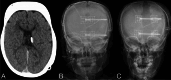

Results: Among 13 included subjects, nine (69.2%) patients had a primary diagnosis of shunted hydrocephalus and 4 (30.8%) patients had IIH. Twelve (92.3%) subjects underwent posterior vault distraction osteogenesis (PVDO) and one (7.7%) underwent posterior vault remodeling (PVR). All 4 patients with IIH demonstrated symptomatic improvement following PVDO, including resolution of headaches, vomiting, and/or papilledema. Among 9 patients with shunted hydrocephalus, CSF diversion requirement decreased from 2.7 ± 1.6 procedures per year preoperatively to 1.2 ± 1.8 per year following cranial vault expansion (p = 0.030). The mean postoperative follow-up was 4.1 ± 2.1 years and four (30.8%) patients experienced complications within 90 days of surgery, including infection (n = 2), CSF leak (n = 1), and elevated ICP requiring lumbar puncture (n = 1). Four (30.8%) patients underwent repeat cranial vault expansion for recurrence of ICP-related symptoms. At most recent follow-up, 7 of 9 patients with shunted hydrocephalus demonstrated symptomatic improvement.